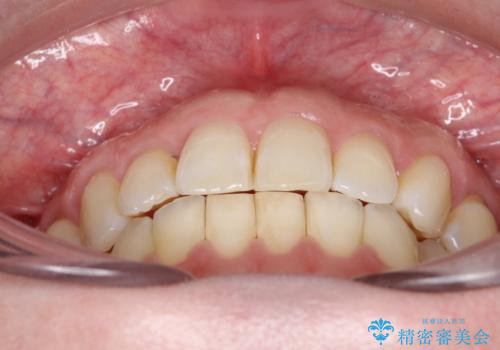

上の歯と下の歯が反対にかんでいる インビザラインによる目立たない矯正

- 右上の前から2番目と3番目の歯が内側に引っ込んでしまっているのを主訴に来院されました。

右上の2番目と3番目のはが前後反対にかんでしまっている状態でした。

インビザラインにて治療することとしました。

内側に引っ込んでいる歯も、インビザラインにてしっかり外側に動かすことができます。